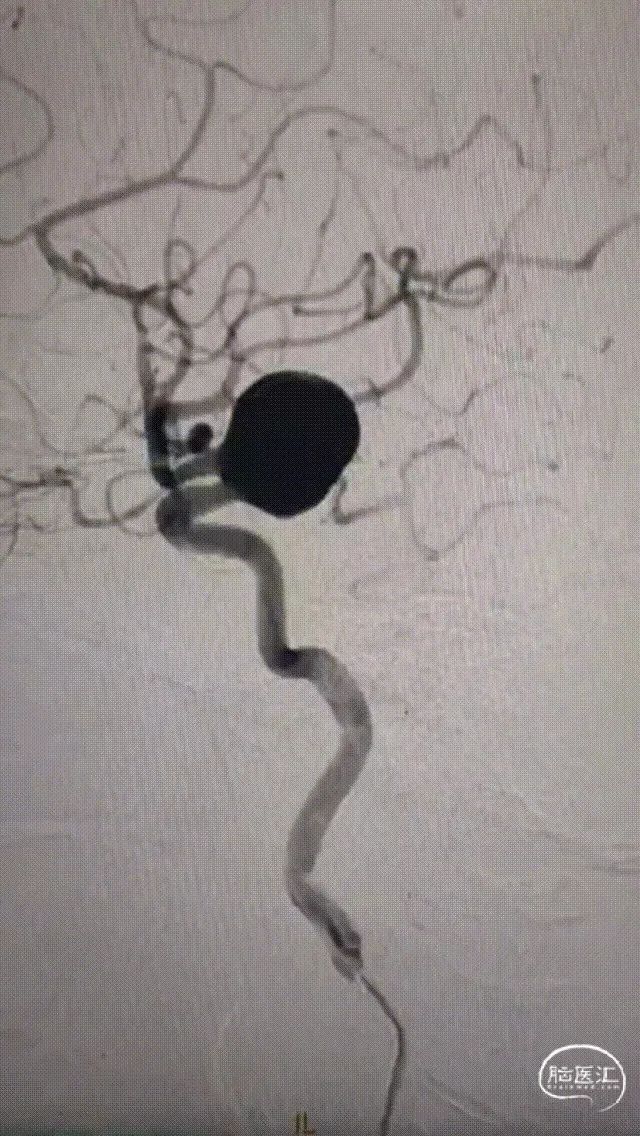

术前影像

脑动脉DSA提示右侧颈内动脉C5床突段动脉瘤。

右侧床突段载瘤动脉远端血管直径为1.8mm,载瘤动脉近端血管直径为5.2mm,瘤体宽13.1mm,瘤体最大宽度21.8mm。